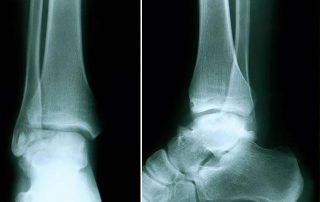

Mężczyzna 21 lat – martwica oddzielająca bloczka kości skokowej

Mężczyzna - 21 lat - leczony z powodu osteochondrosis dissecans ossis talii (martwica oddzielająca bloczka kości skokowej). Leczony przez pięć lat zachowawczo w innym ośrodku. Wykonałem artroskopię, znalazłem 4 ciała wolne chrzęstne oraz 2 fragmenty kostno-chrzęstne.